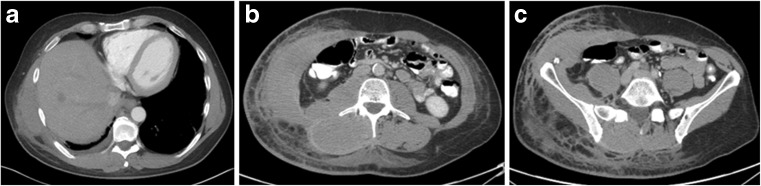

Fig. 3.

a, b, c Contrast CT images at the level of the lower chest, mid abdomen and pelvis show asymmetric diffuse soft tissue stranding and thickening consistent with tumor spread in the skin, subcutaneous soft tissue and musculature